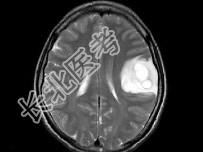

- 单项选择题女,33岁, 3个月前有右上肢及右颜面部麻木,伴耳鸣及头昏, 根据所提供图像,最可能的诊断是 ( )

A、脑脓肿

B、星形细胞瘤

C、脑结核

D、脑转移瘤

E、脑血吸虫病